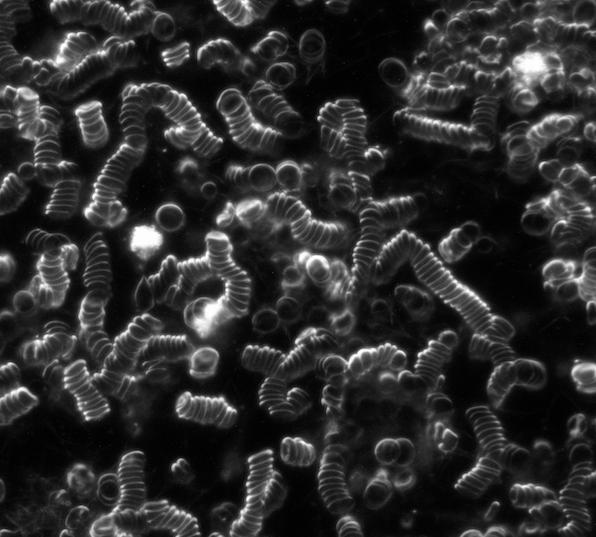

Vitalblutanalyse

Vitalblutanalyse

Vitalblut im Dunkelfeld Lichtmikroskop mit Geldrollenbildung

Vitalblut im Dunkelfeld mit diversen Auffälligkeiten

Symplast im Blut

Hier müssen mehrere Ebenen mit verschiedenen Schärfen betrachtet werden,

um eine Verunreinigung des Objektträgers auszuschließen